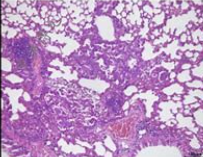

肺纖維化模型病理及纖維化檢測: